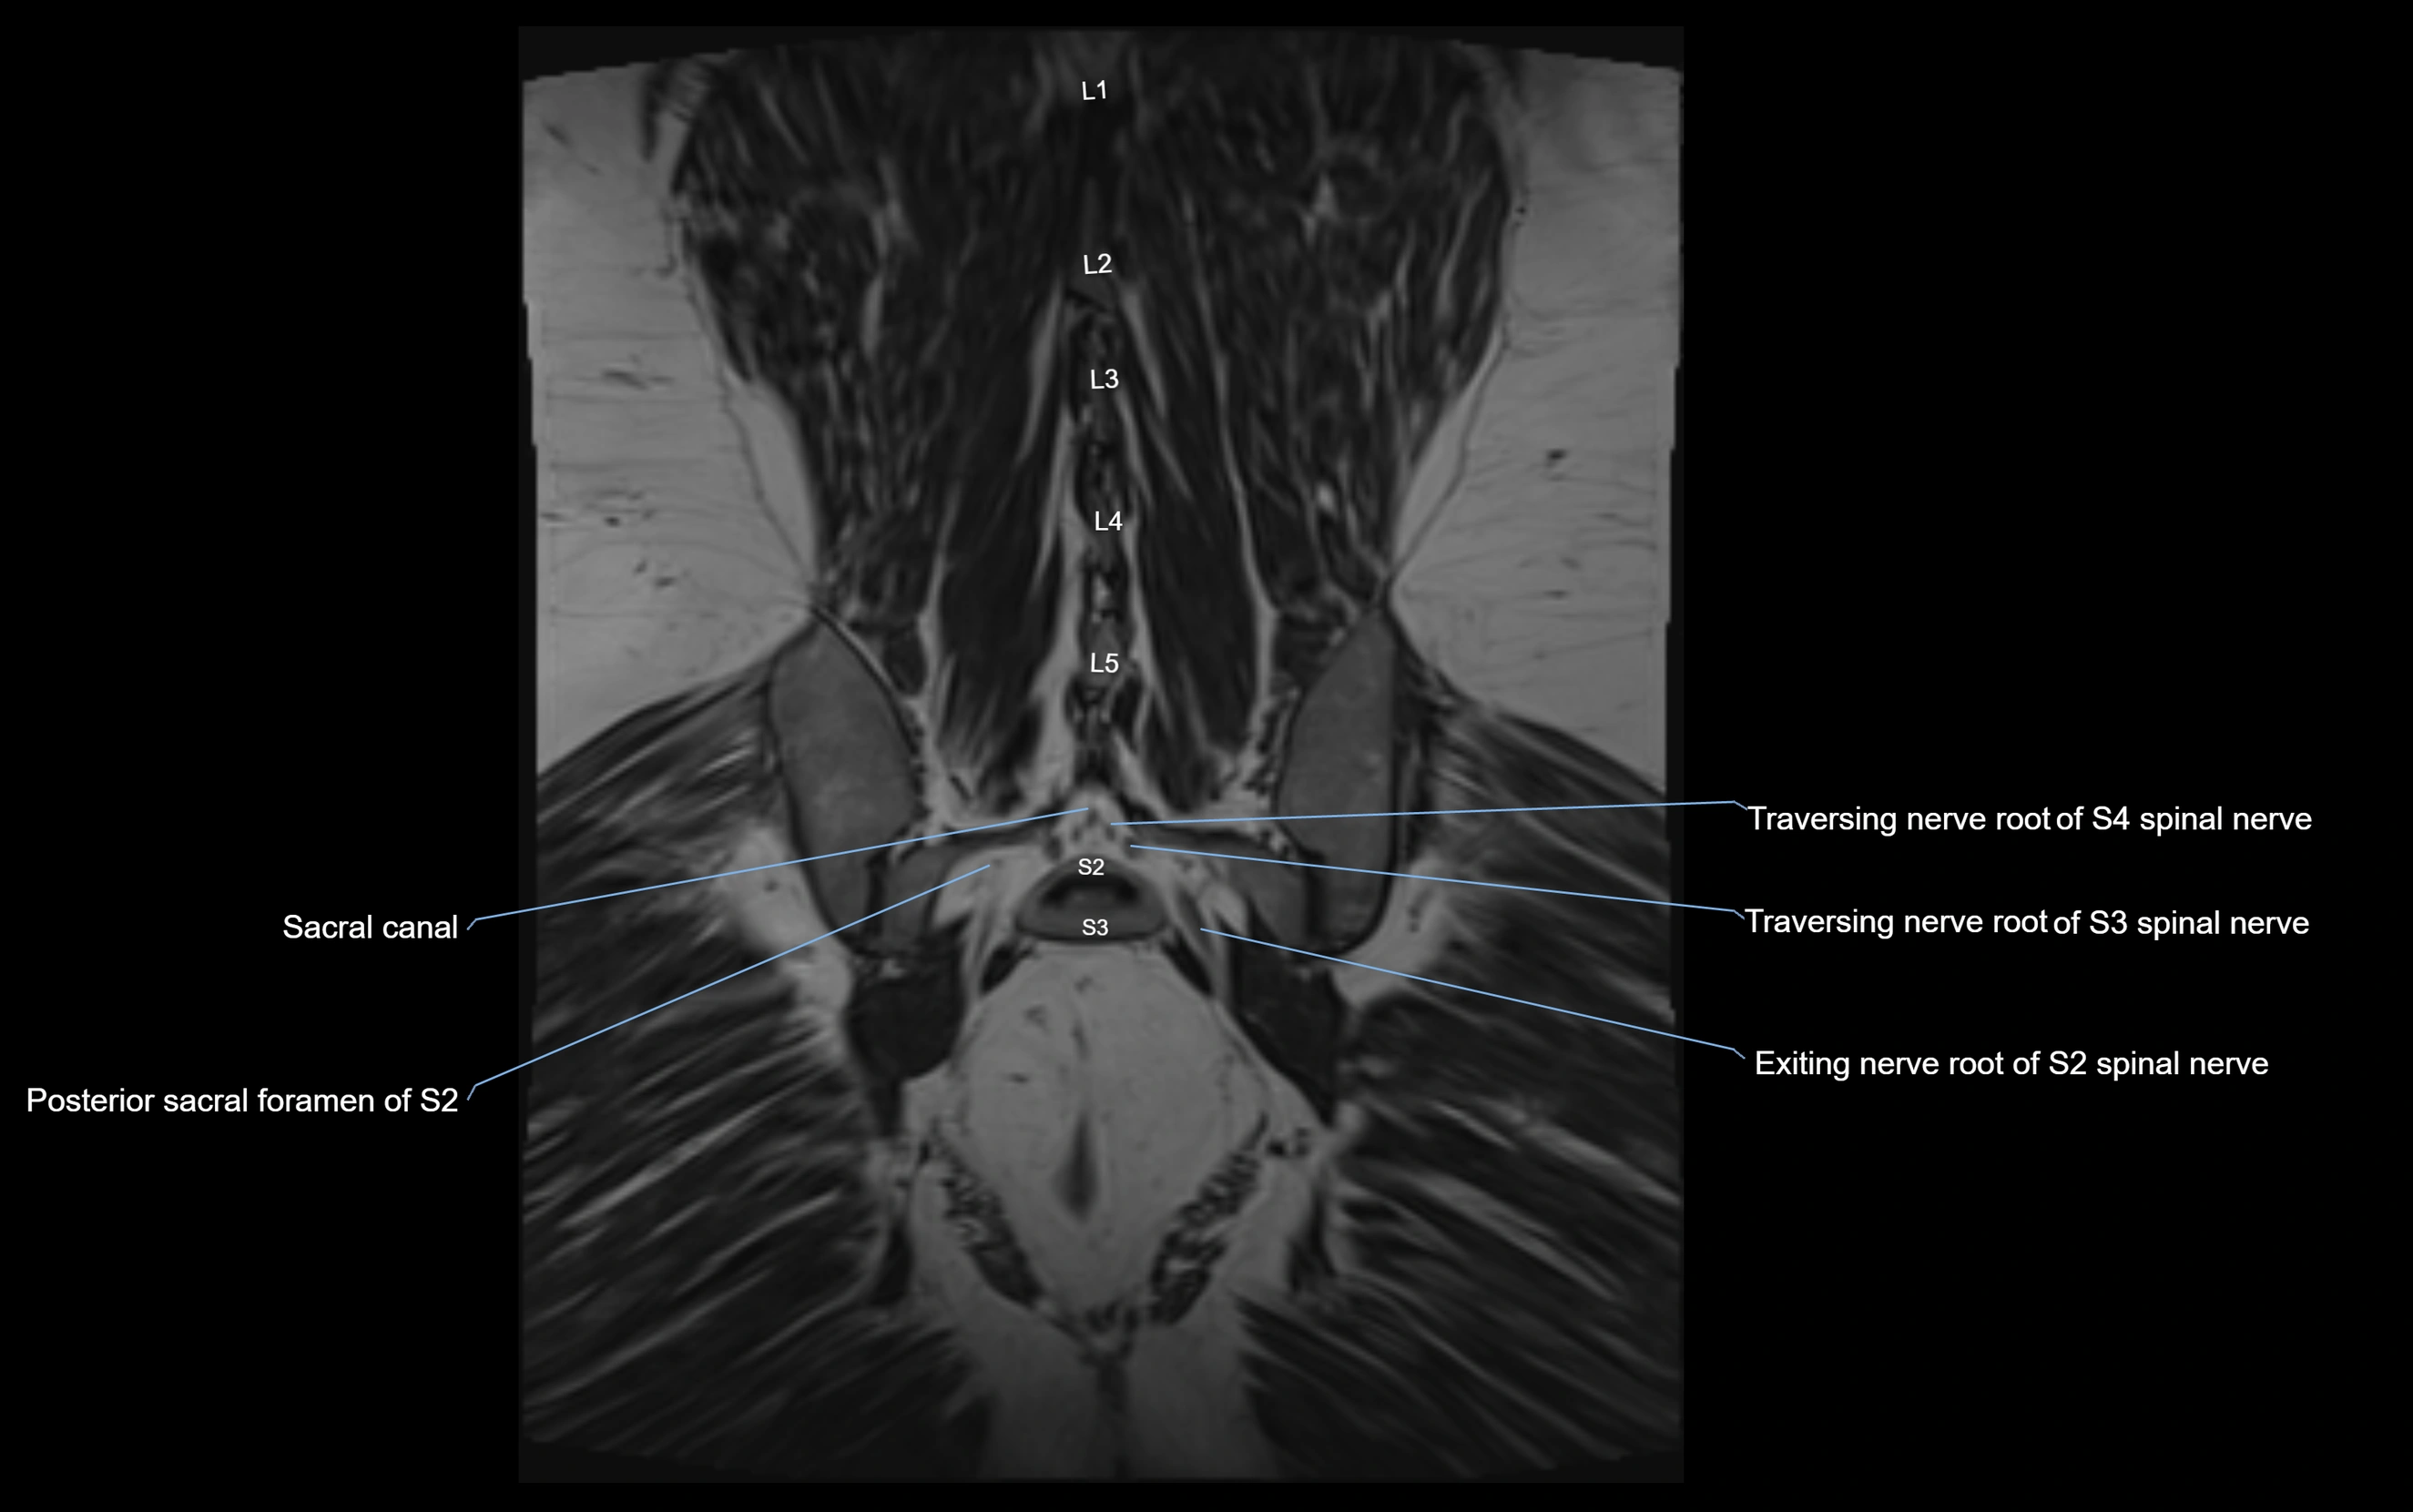

MRI Appearance

T1-weighted images:

• Nerve appears as a very thin low-to-intermediate signal intensity structure

• Surrounded by bright fat, aiding visualization

T2-weighted images:

• Nerve shows intermediate to mildly hyperintense signal compared to muscle

• Pathological involvement appears brighter

STIR (Short Tau Inversion Recovery):

• Normal nerve appears dark

• Inflamed or entrapped nerve appears bright hyperintense

T1 Fat-Sat Post-Contrast:

• Normal nerve enhances minimally

• Pathologic nerve (neuritis, entrapment, tumor infiltration) shows focal or diffuse enhancement

3D T2 SPACE / CISS:

• Nerve appears intermediate to mildly hyperintense compared to muscle

• Surrounded by bright fat or CSF, improving visualization

• Best sequence for mapping small pelvic nerves such as the anococcygeal

MRI image

image